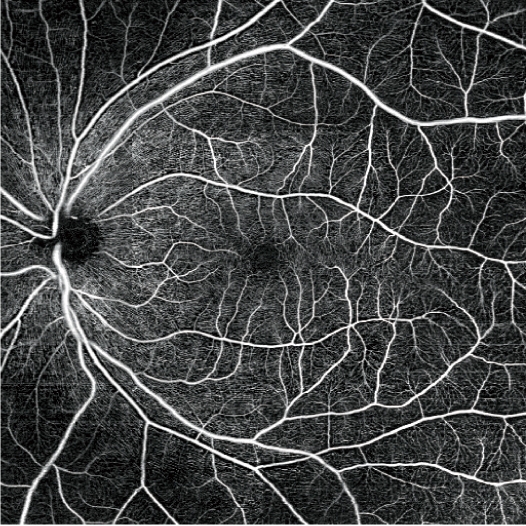

全面的OCT-血流成像和診斷

界面簡潔,黃斑地形圖分七層分析,視盤地形圖分四層分析,功能直觀,可去除投射的偽影。分成多個板塊可以增強對特定深度和感興趣區域的視網膜微血管系統的評估。

黃斑AngioScan:黃斑地形圖

-玻璃體、淺層、深層、視網膜外層、ORCC、脈絡膜毛細血管層、脈絡膜

視乳頭AngioScan:視盤地形圖

-玻璃體、視神經頭、視盤周圍放射狀毛細血管叢 (RPCP)、篩板

圖片由Alejandro Villalobos醫生提供